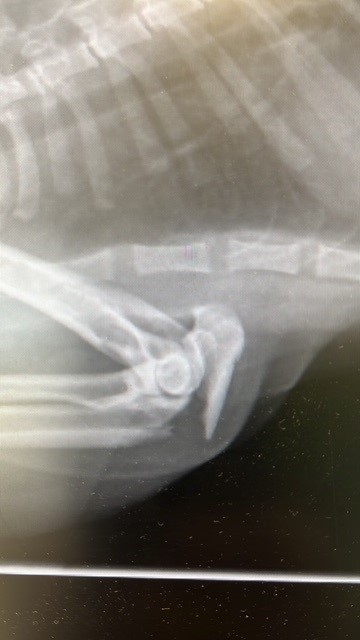

Diagnose: Komplizierte Femur- und Ellenbogenfraktur links

Therapie: operative Fixierung mittels Pin, Zugschraube, Schrauben und Platten

Als der junge Kater Mischu nach einem mutmasslichen Autounfall schwer verletzt aufgefunden wurde, zählte jede Minute. Die Diagnose war erschütternd: eine komplizierte Fraktur am linken Femur und am linken Ellenbogen. Mischu hatte starke Schmerzen und brauchte dringend eine aufwendige Operation sowie eine längere Nachbehandlung.